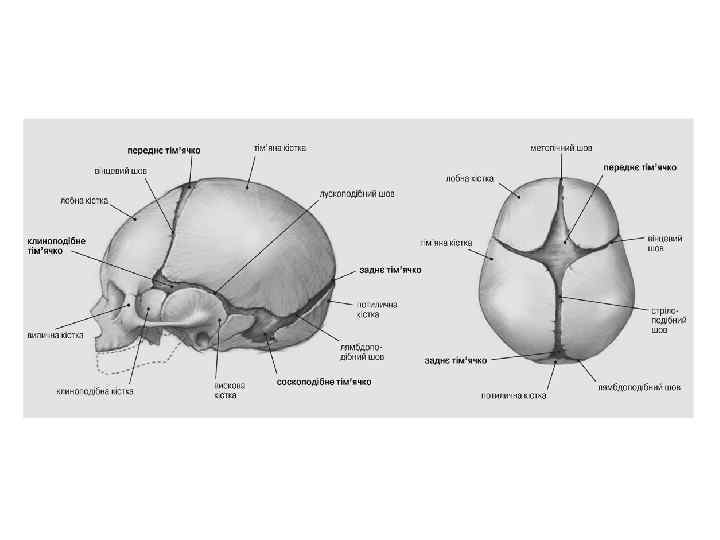

Череп (cranium)

Череп (cranium)

Череп (cranium)

Череп (cranium)

Череп (cranium)

Череп (cranium)

Череп (cranium)

Череп (cranium)

Череп (cranium)

Череп (cranium)

Череп (cranium)

Череп (cranium)